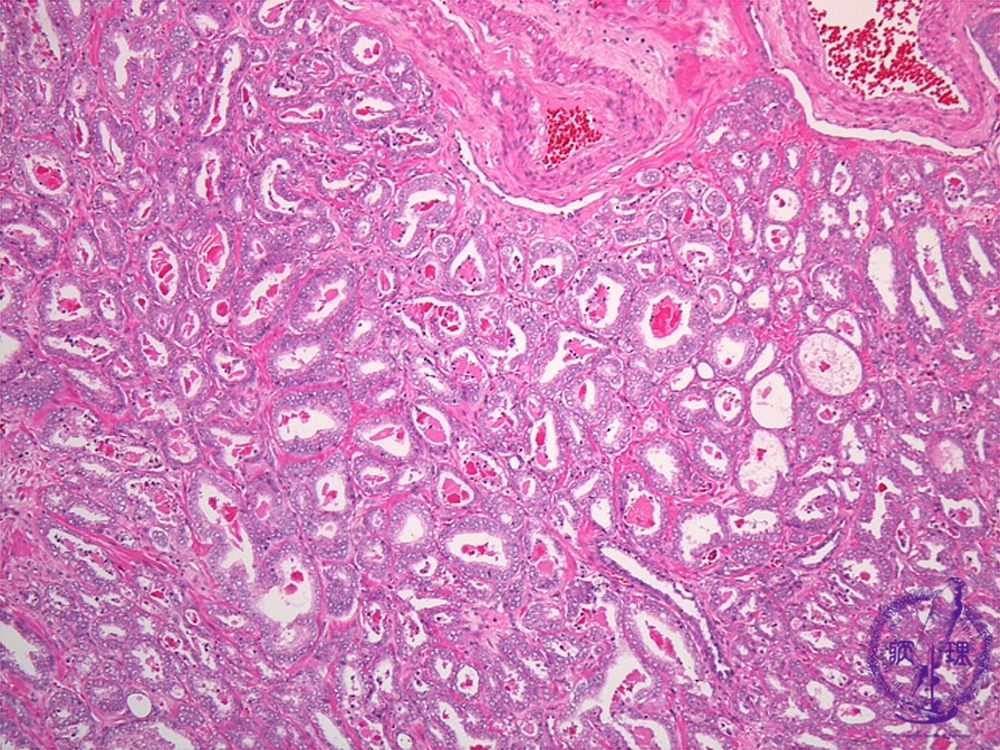

- (2)Prostatic cancer (adenocarcinoma, Gleason grading system)

Histology (HE stain, intermediate power): Well differentiated adenocarcinoma. According to the degrees of tubular structure conservation, the histological degree of differentiation has been classified as well, moderately or poorly differentiated. However, at this juncture, Gleason grading system is common as a means of evaluating prognosis. The Gleason score of this case 6(3+3).